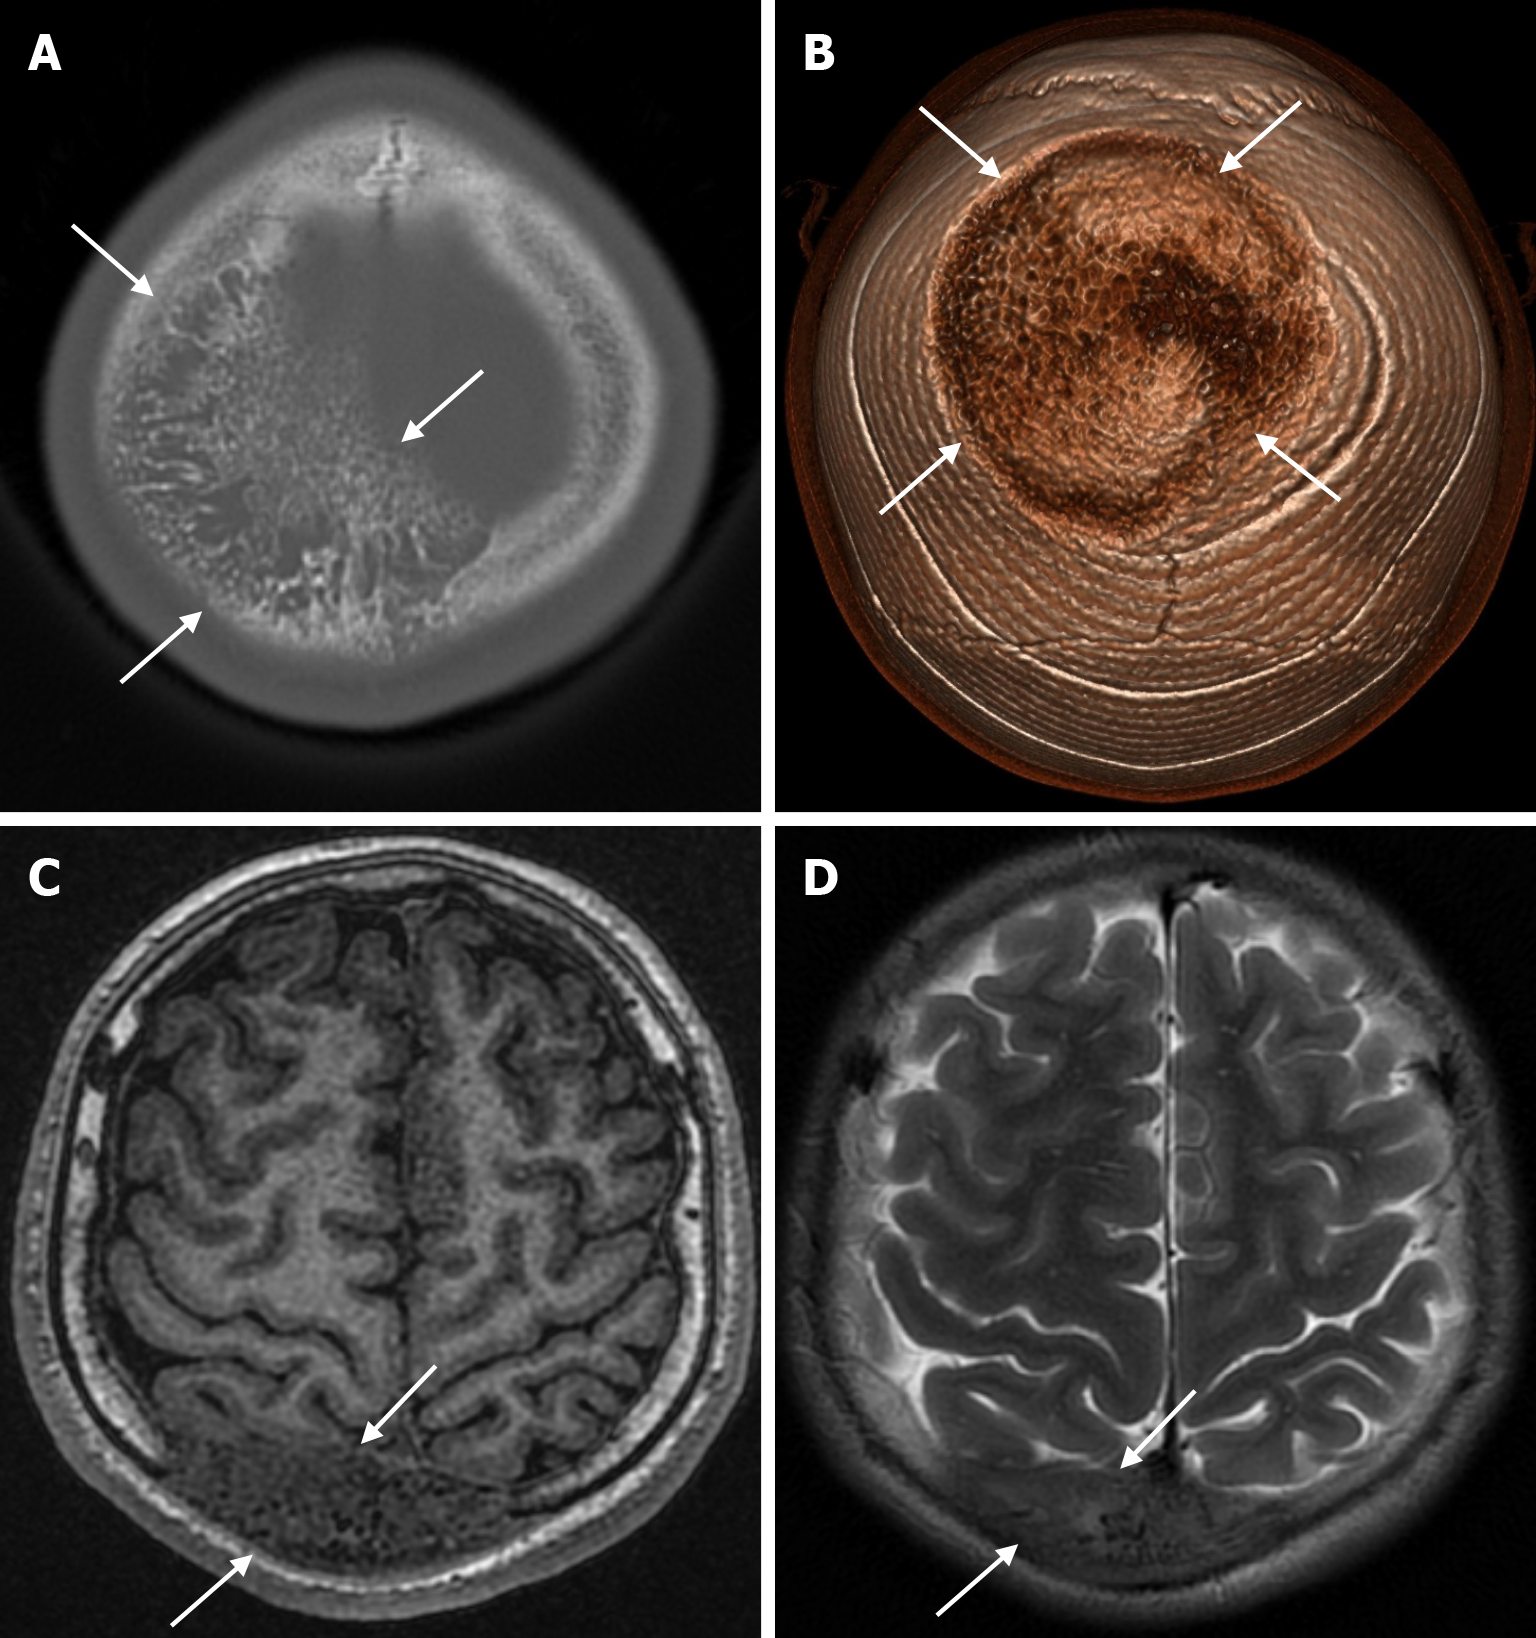

Lacunar skull, also known as Lückenschädel, is a fetal ossification disorder described in the early 19th century and rarely seen as an isolated defect. In this ossification defect, shallow or deep cavities form in the flat bones of the inner table of the skull due to mesenchymal dysplasia during intramembranous ossification. Lesions can be seen in any part of the skull but are more prominent in the frontal, parietal, and upper occipital bones. Lacunar skull development begins in utero but disappears by six months. Although it is not usually associated with any medical problem, it is painful when applied to the skin with local pressure, and these patients are at greater risk of brain damage from local trauma. Lacunar skull is often associated with neural tube defects, including spina bifida, meningocele, myelocele or encephalocele. Other congenital developmental anomalies such as rib and limb deformities, microcephaly, cleft palate and craniosynostosis may be present. A direct radiograph reveals that the craniolacuna has a distinctive "honeycomb" or "soap bubble" appearance. Large, rounded areas of reduced bone density are bordered by a pattern of thick bone that resembles a spiderweb. However, three-dimensional CT clearly shows numerous oval and round lacunae[17].

The beaten copper skull shows prominent convolutional markings on several bones of the skull. These convolutional markings normally appear between the ages of 2-3 and 5-7 years, which are periods of rapid brain growth. The occurrence of convolutional markings in children younger than 18 months should suggest a cause leading to increased intracranial pressure due to processes such as obstructive hydrocephalus, craniosynostosis or intracranial masses. Beaten copper skull pattern develops because of pressure applied to the soft skull by the growing brain. The beaten copper skull is usually confined to the posterior part of the inner table of the skull, but this appearance can affect the entire skull. Plain radiography of the skull can be an important diagnostic tool to detect increased intracranial pressure. In children, CT and three-dimensional reconstructions are best used to evaluate the convolutional markings (Figure 5) and cerebral ridges for surgical planning[23].

Skeletal changes in chronic anemia are due to ineffective erythropoiesis as a result of impaired haemoglobin synthesis, peripheral destruction of erythrocytes and consequently reduced erythrocyte lifespan. Radiography show massive hyperplasia of the bone marrow associated with hyperactivity of the bone marrow in response to anemia. The hair-on-end sign is seen on plain radiography of the skull, CT and MRI as long, thin vertical lines of calcified spicules perpendicular to the bone surface, appearing as upright hairs. The hair-on-end appearance of the skull is a characteristic feature of chronic haemolysis, usually seen in patients with thalassaemia (Figure 14) and sickle cell disease. The incidence of hair-on-end appearance in patients with thalassaemia is 8.3%. Although rare, the hair-on-end sign has also been described in iron deficiency anemia, sickle cell disease, cyanotic congenital heart disease, hematological malignancies and nutritional deficiencies. The appearance of these projections indicates excessive medullary erythropoiesis in patients and is rare before the age of 5 years. As the bone lesions are explained by the relationship between proliferating bone marrow and bone cortex, only hypertransfusion initiated early in life will prevent the development of the abnormality[55].